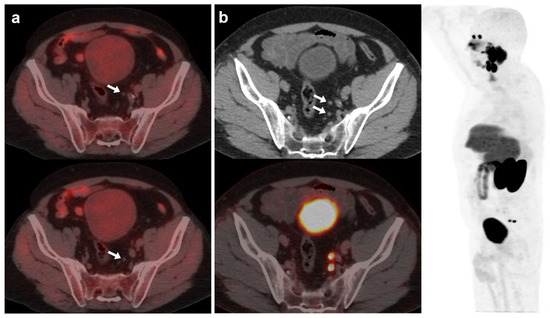

On the other hand, [18F]DCFPyL was positive alone in 48/89 (53.9%) patients, being oligometastatic in 25 (Figure 2). Five patients were exclusively positive with [18F]F-choline-PET/CT, and thus, [18F]DCFPyL down-staged [18F]F-choline results from positive to negative (3 follow-up, 1 biopsy (negative) and 1 ADT). [18F]DCFPyL up-staged 5/21 patients with oligometastatic disease on [18F]F-choline-PET/CT to polimetastatic disease after [18F]DCFPyL.

Figure 2.

67-year-old patient. Gleason 7 PCa treated with RP. First BCR treated with prostate fossa radiotherapy. Second BCR (PSA 0.63 ng/mL, PSAdt 8.6 months, PSAvel 0.04 ng/mL/month) scanned with [18F]F-choline (a) and [18F]DCFPyL PET/CT (b), time window of six days. Lymph nodes metastases (white arrows) were demonstrated only on [18F]DCFPyL scan, changing therapeutic management (escalation). Patient underwent lymph nodes SBRT. PSA level decreased.